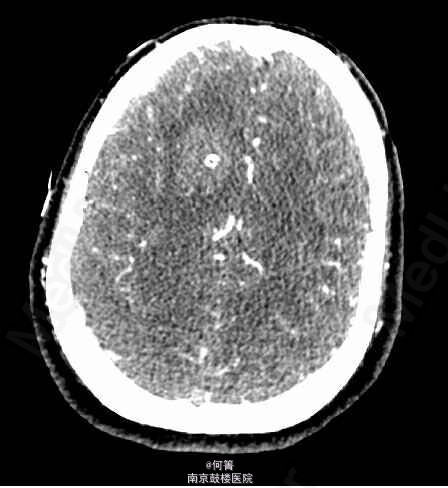

患者,女,59岁,因“突发头痛伴意识障碍4天”入院。入院前4天,患者无明显诱因突发头痛,伴有恶心、呕吐,呕吐多次胃内容物,继之出现意识障碍,呼之不应,小便失禁,无四肢抽搐,送至当地院就诊,行头颅CT示颅内出血,予侧脑室外引流穿刺及输液治疗,患者意识逐渐恢复,转至我院进一步治疗。既往高血压病史4年。

查体:BP:158/103mmHg,余生命体征平稳。专科查体:嗜睡状,呼之能应,查体欠合作;右侧额部留置有脑室外引流管,引出淡红色脑脊液;颈项强直。 辅助检查:CTA:蛛网膜下腔出血,脑室积血,右侧额叶血肿伴灶周水肿,脑实质明显肿胀,中线局部左移,右侧脑室见引流管。基底动脉瘤,其内密度不均匀,可疑血栓形成,大小约1.0x1.5cm;左侧椎动脉颅内段动脉瘤,大小约0.6x0.5cm;左侧大脑中动脉M1及M2D段交界区动脉瘤,截面大小约0.6*0.6厘米;右侧颈内动脉终段、左侧大脑中动脉M1段及椎动脉管腔不均匀,局部增粗,管壁欠光整。